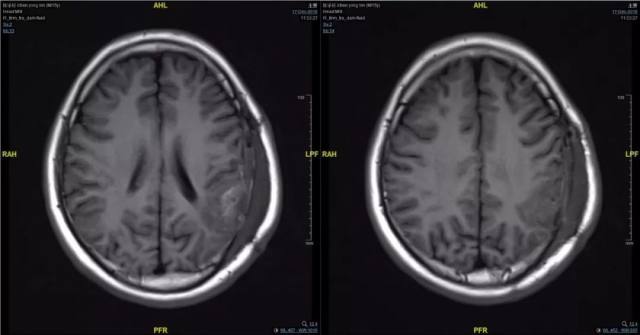

2、术前影像资料

图 1 术前 CT:左颞顶枕术后;局部混杂密度影,考虑出血伴钙化,请结合临床。

图 2 术前 MRI:左颞顶枕血管畸形术后;混杂信号;考虑畸形残余伴出血。